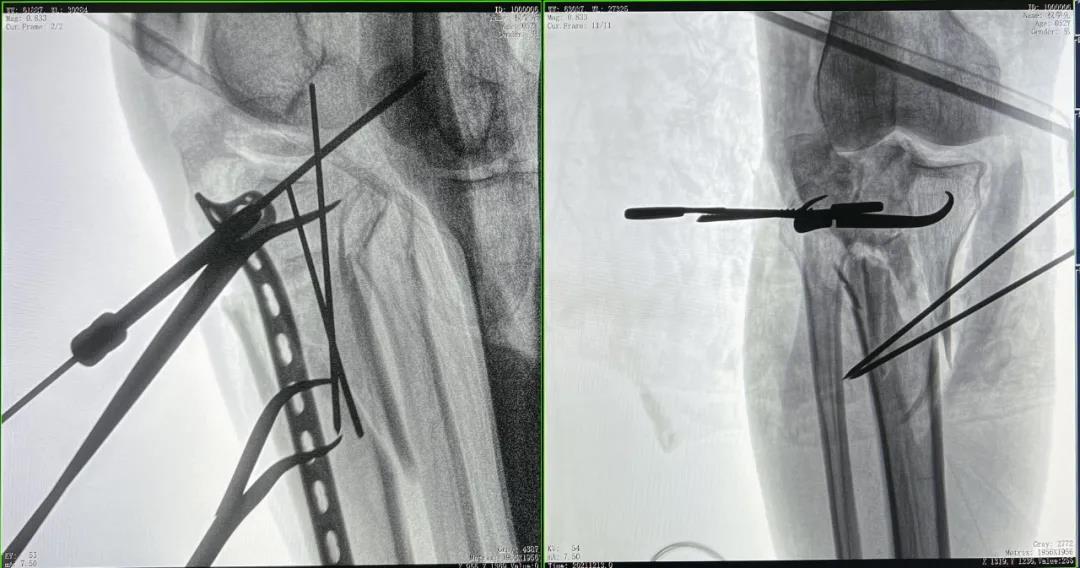

優質的術中影像輔助螺釘準確植入